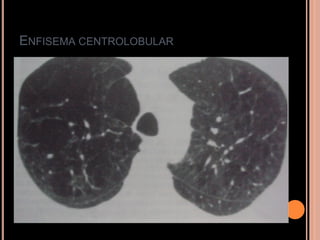

ENFISEMA CENTROLOBULAR

   Múltiplas áreas redondas de atenuação

anormalmente baixas ( mais em LS);

   Áreas de radiotransparência geralmente próximas

ao centro dos lóbulos pulmonares envolvendo os

ramos das artérias centrolobulares;

Eventualmente podem ser vistas paredes finas

relacionadas à fibrose adjacente;

Mais grave  confluência  enfisema centrolobular

confluente (simula enfisema panlobular);